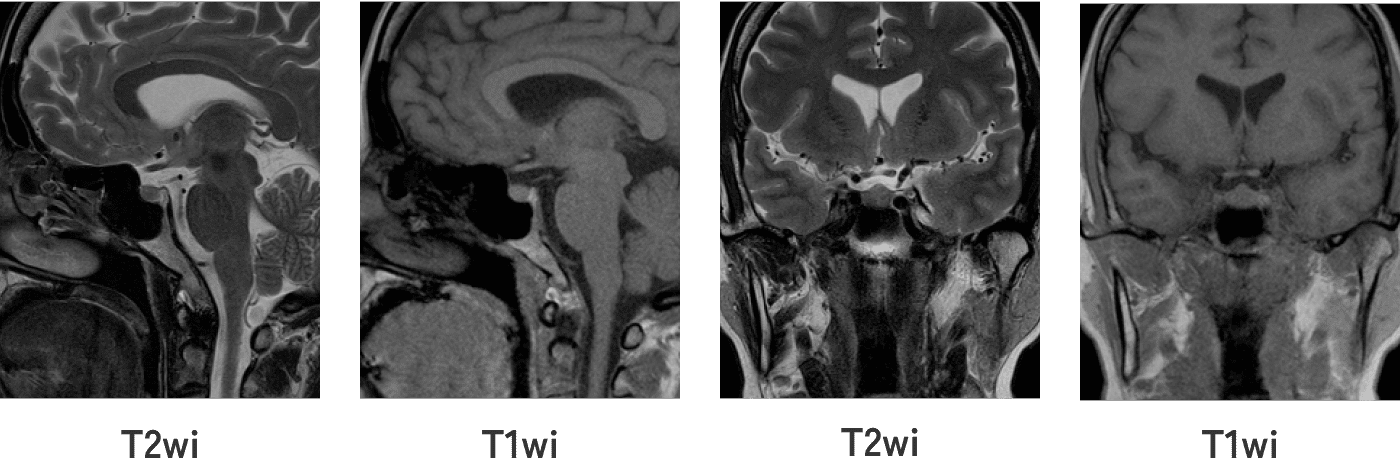

20220914082754.jpg。放射線科|八潮中央総合病院。正常画像と並べてわかる腹部・骨盤部MRI―ここが読影のポイント。対象検査部位・撮像手法|UNB住吉神社前クリニック 放射線科。「腹部のMRI」荒木 力定価: ¥ 13000#荒木力 #荒木_力 #本